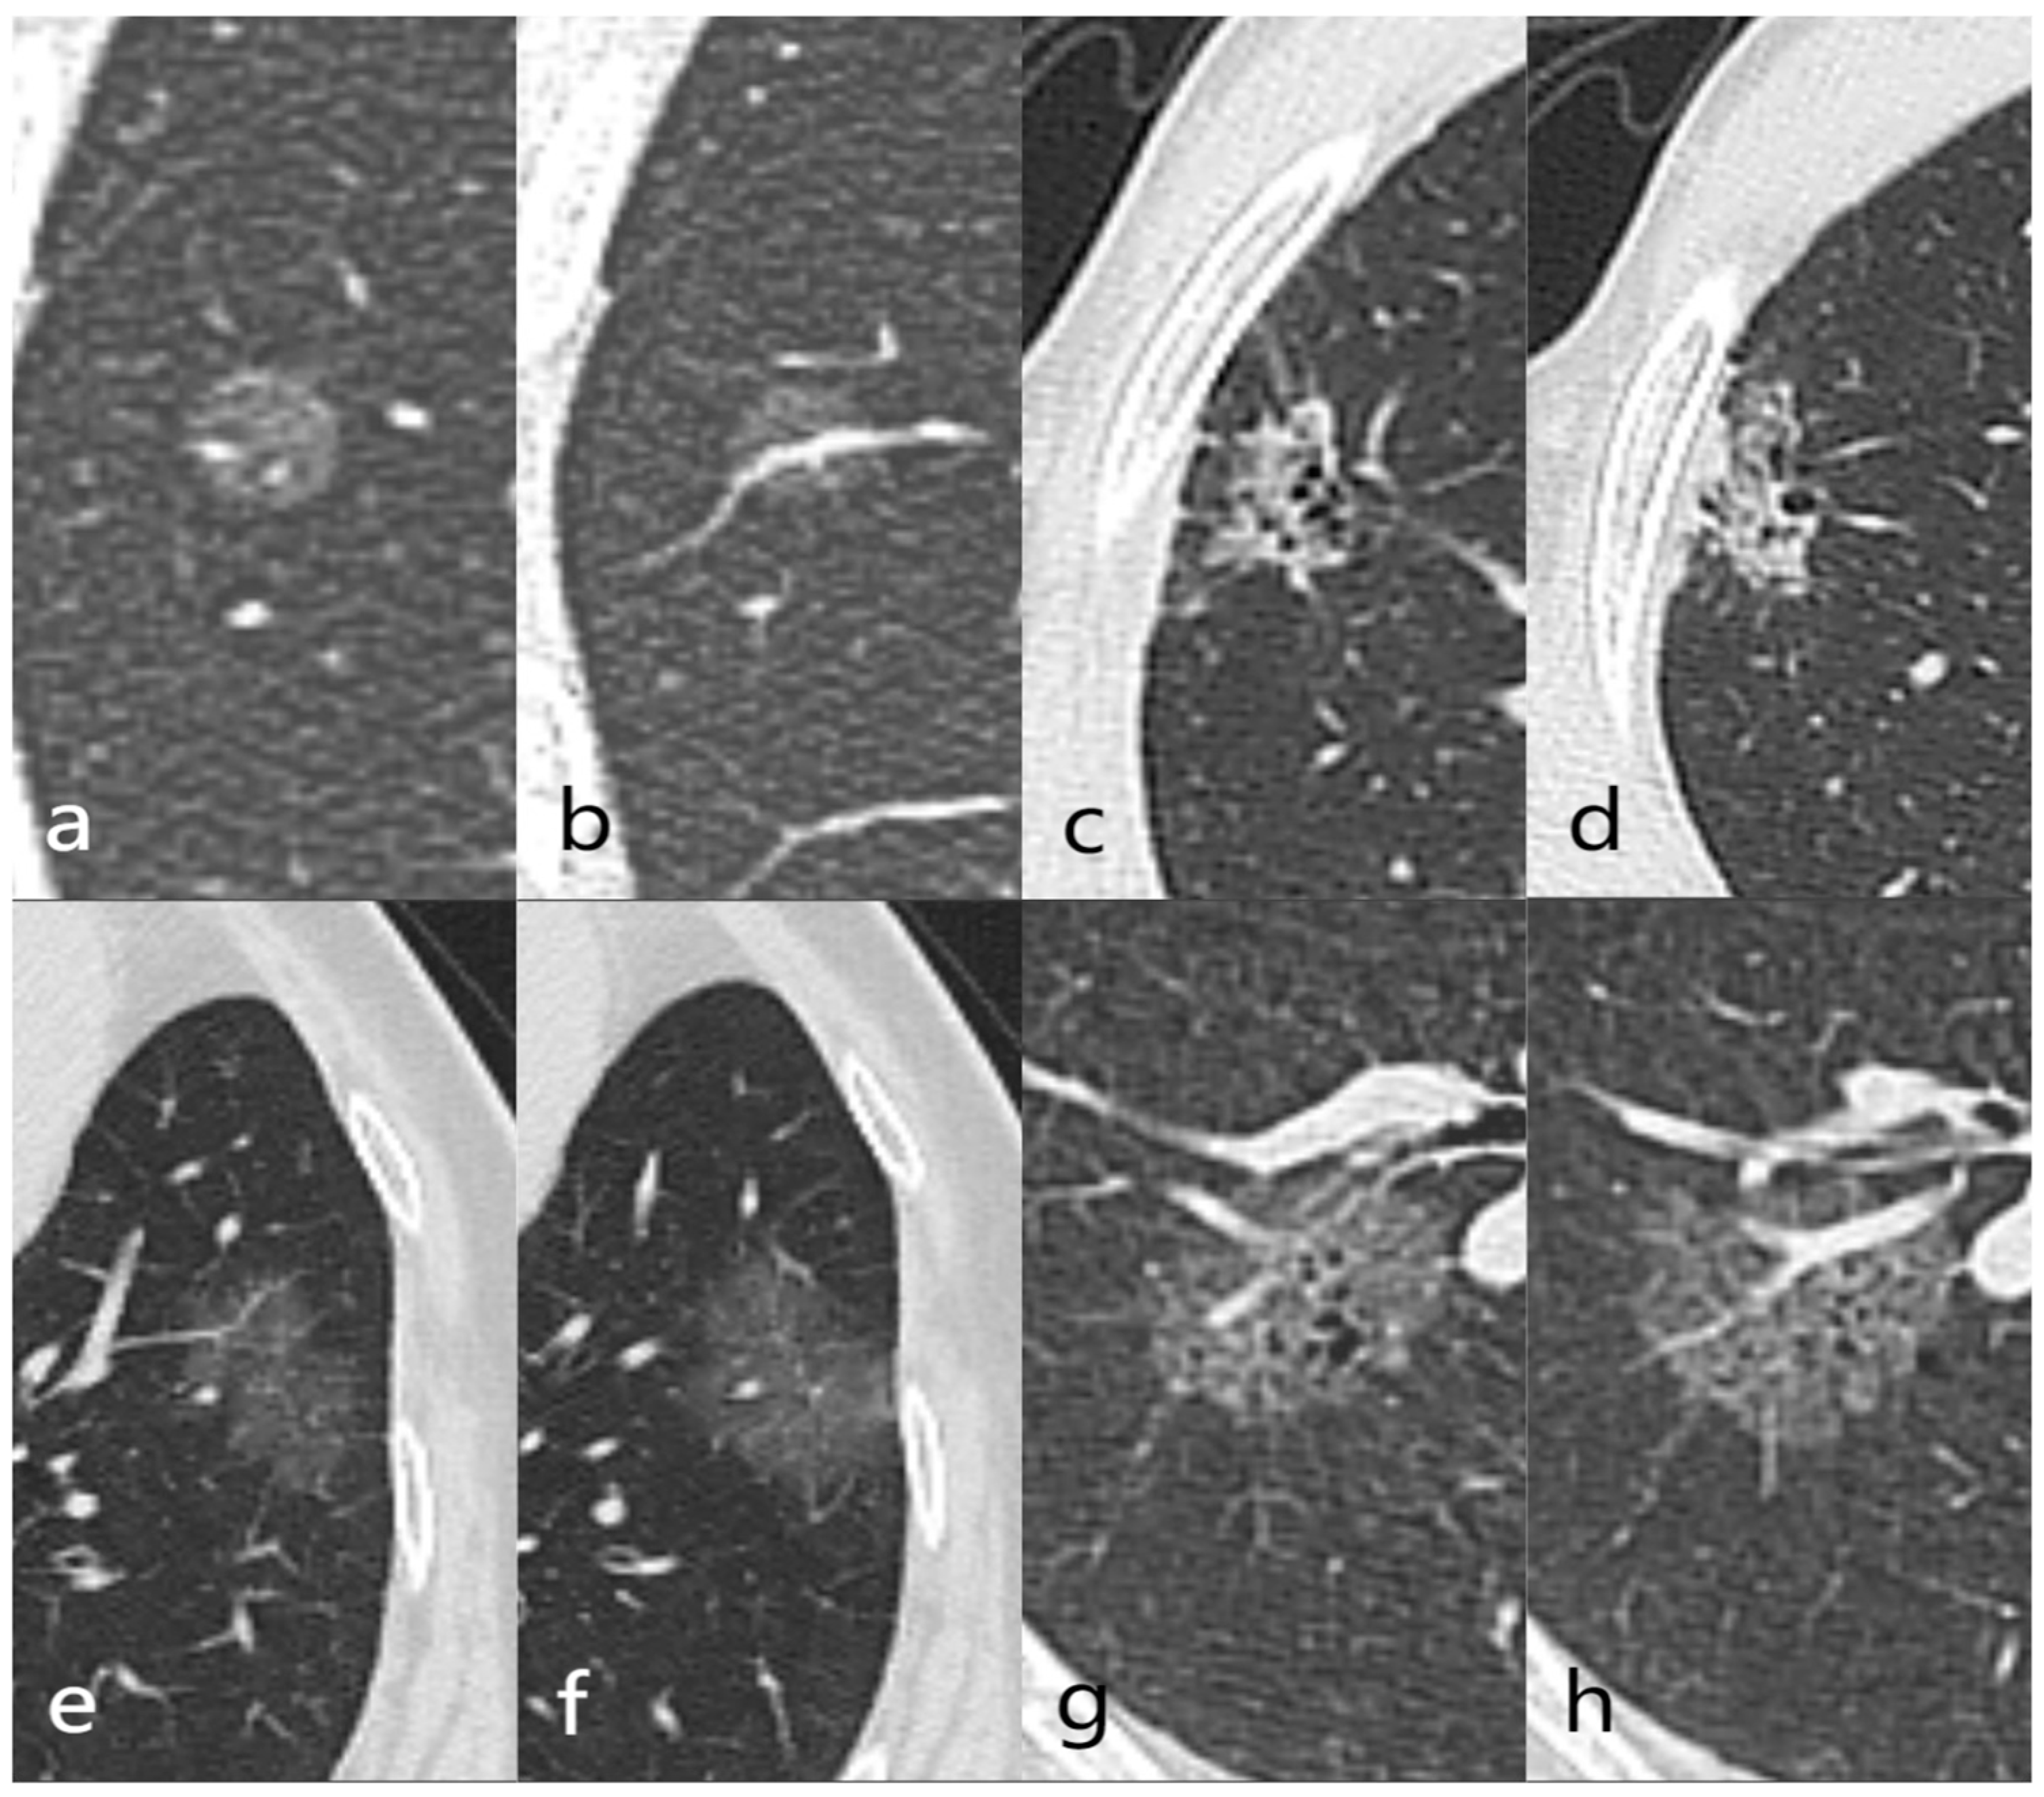

3.1. General Information and CT Imaging Features

3.3. Construction and Diagnostic Performance of Predictive Models